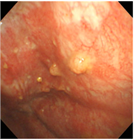

1. 胸腔鏡で腫瘍が確認されない最も早期の胸膜中皮腫である”mesothelioma in situ(前浸潤性中皮腫)” の存在は以前から知られていたが、『WHO分類 第5版』に初めて明記された。